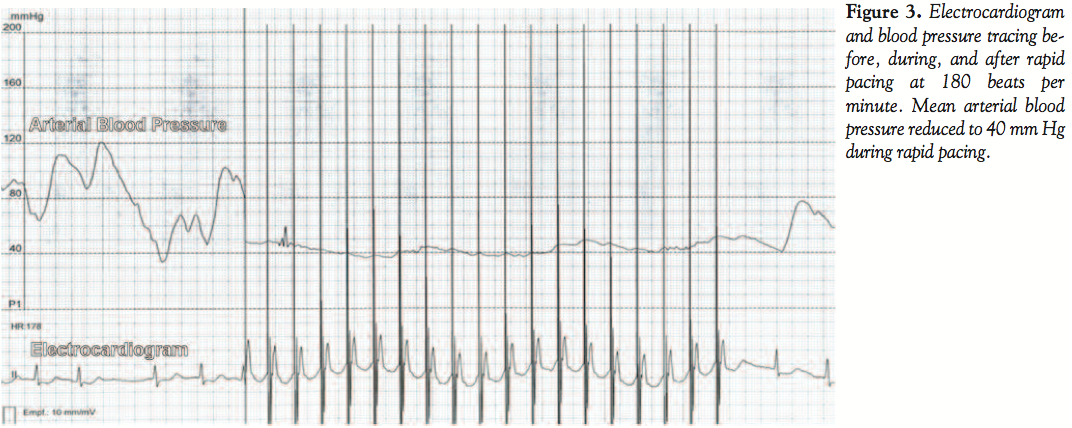

The ostium of the LM stem was engaged using the same 5 Fr guiding catheter and guidewire. The tip of the wire was positioned into a septal branch of the LAD. The distal LM and ostial LAD were predilated using the same balloon at 24 bar. An Orsiro 3.0 x 9 mm stent (Biotronik AG) was placed in the lesion. The external end of the Magnum guidewire was connected to the cathode (negative pole) of a single-chamber Medtronic 5348 temporary pacemaker (Medtronic, Inc) with an alligator clamp, whereas the anode (positive pole) was connected to a large surface skin electrode at the left thigh of the patient. Pacing was instituted at 180 beats per minute, with output set at maximum (20 mA) and sensitivity turned off. The awake patient felt no discomfort. During rapid pacing, the stent was deployed using 14 bar for an inflation duration of 10 seconds (Figure 2). The mean arterial pressure was decreased to 40 mm Hg and the pulse wave to around 10 mm Hg (Figure 3). Rapid pacing was stopped with balloon

deflation. Angiography revealed a good result in the distal LM stem and ostial LAD, but the ostial LCX was now compromised owing to the carinal plaque shift (Figure 4). The Magnum guidewire was therefore repositioned across the ostial LCX into the first obtuse marginal branch of the LCX and the 3.0 x 9 mm stent balloon was used to fenestrate the side branch (ostial LCX) with 20 bars. Because the result was suboptimal, a second Orsiro 3.0 x 9 mm stent was positioned with its proximal portion located at the junction of the LM stem with the ostial LCX. The external portion of the Magnum guidewire was again connected to the temporary pacemaker and rapid pacing was instituted at 180 beats per minute to optimally position the stent at 14 bar (Figure 5). An excellent angiographic result was achieved in the LCX, but there was slight impingement of the ostial LAD (not shown). Therefore, the LAD was rewired and the ostial LAD was postdilated using the 3.0 x 9 mm stent balloon. An excellent angiographic result was achieved (Figure 6).